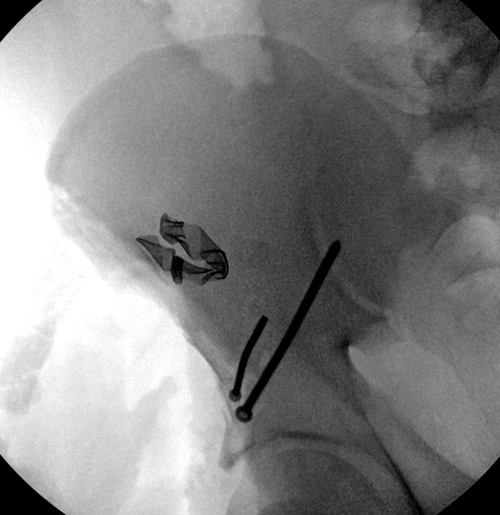

Представленные слайды Александром из Севастополя, имеет ценность, но, кроме inlet, остальные стандартные Judet рентген снимки должны показать правоту принятого решения. Возможно, здесь фиксация перелома вертлужной впадины, но по рентгену трудно понять!

Вместо огромного аппарата, пластина на крыле и винты через AIIS (anterior inferior iliac spine) из места прикрепления прямой мышцы создали бы более элегантную фиксацию. Насчет отсутствия материала, неужели рядом с “Москоу-сити”, в областном центре, где рекламируются передовые платные услуги, отсутствует элементарные пластины и винты? http://bsmp40.ru/services/pay/travma

Фиксация переломов передней колонны намного легче, чем остальных переломов вертлужной впадины. Любой доступ: Smith Petersen, Stoppa или ilio-inguinal. Как фиксировать перелом зависит от желания врача, можно пустить пластину по pelvic brim (linea terminalis) или более щадящее из верхнего окна пластиной, а переднюю колонну длинными межколонными винтами.

Здесь пример перелома передней стенки, где сохранен принцип фиксации передней колонны. Для доступа Smith Petersen с остеотомией ASIS. Мышца сарториус отодвинута, и сделана ре-фиксация на свое место винтами. При хорошем обзоре, наличие Farabeuf или Jungblud forceps облегчит репозицию.